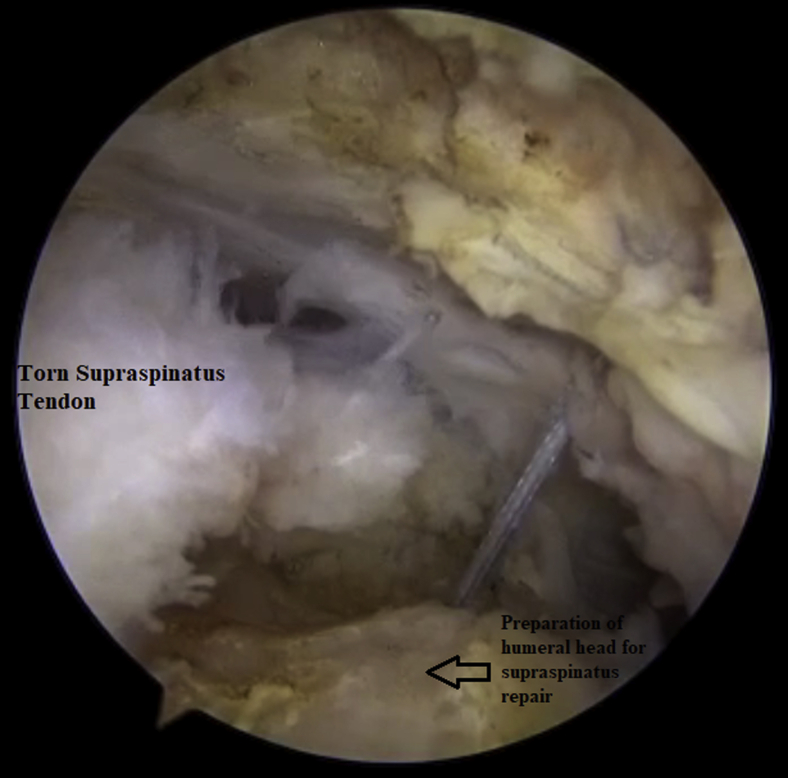

Fig 2.

Debridement and preparation of humeral head for torn supraspinatus tendon repair and anchor placement.

Next, an anterolateral working portal is created through the most superolateral aspect of the rotator interval to reach the posterior aspect of the rotator cuff and to allow more optimal anchor insertion. Application of the Coblation device is performed, followed by the use of a shaver in the subacromial space for subacromial bursectomy, as well as debridement of the superior aspect of the torn supraspinatus tendon, under direct vision (Fig 2). After subacromial bursectomy and better visualization of the greater tuberosity, the humeral head is debrided using the Coblation device and the torn supraspinatus tendon is further prepared using a cutter (Arthrex).